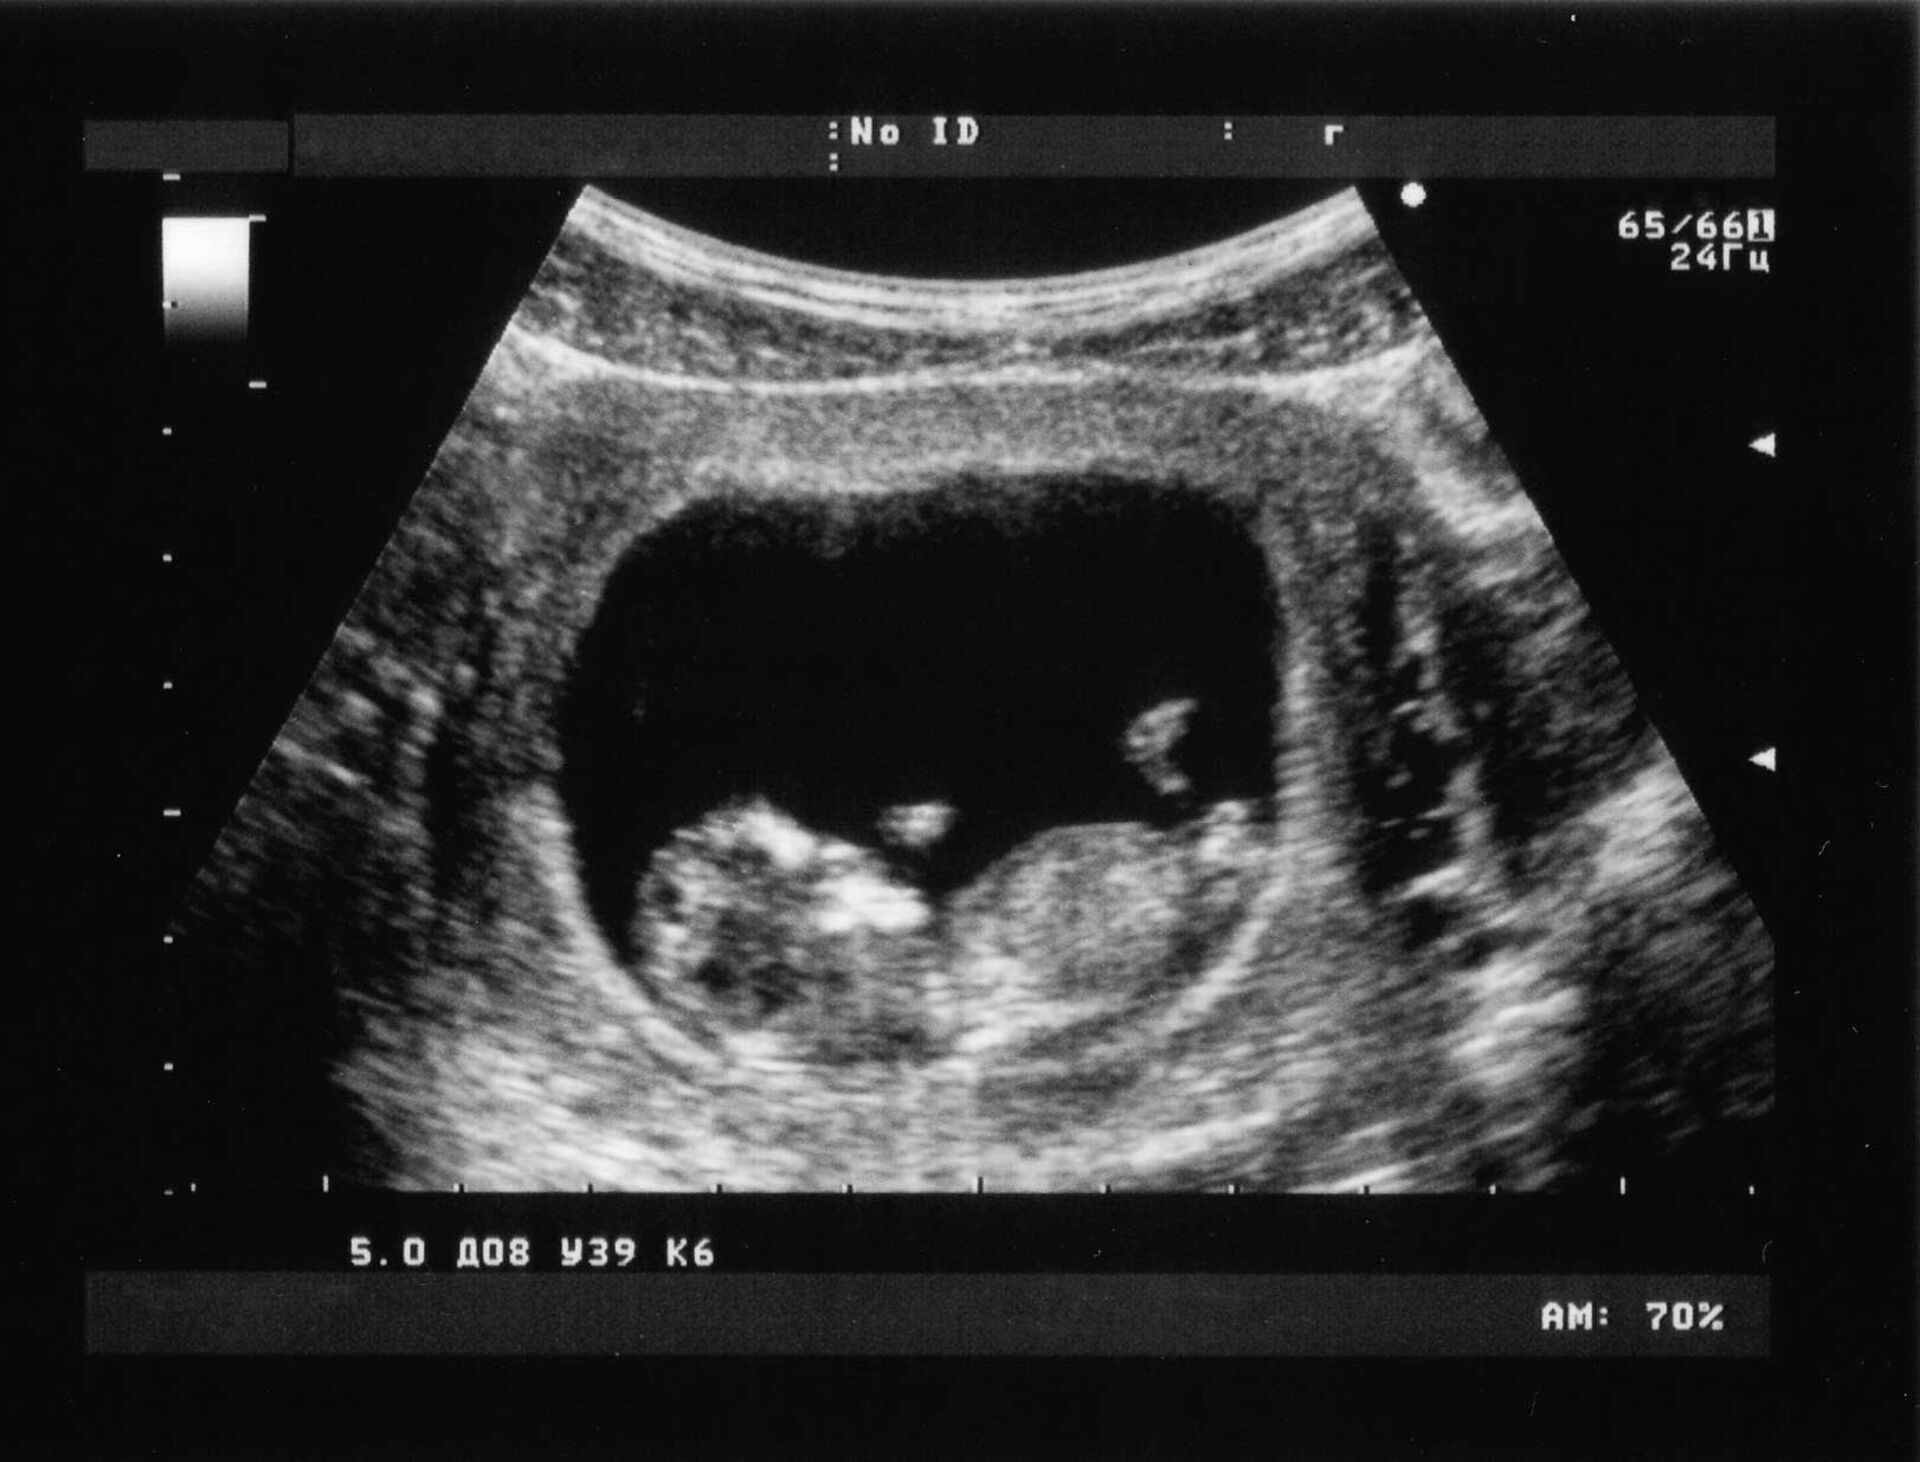

«Leistungen bei Mutterschaft»

Welche Leistungen übernehmen die Krankenkassen in der Schweiz?